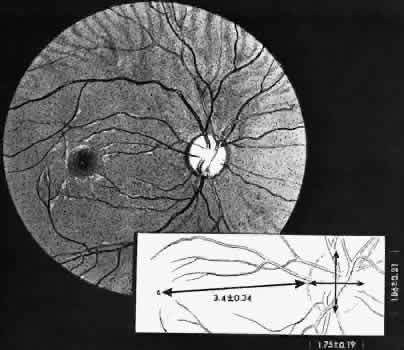

Precise measurements of the optic disc diameter and the disc-to-fovea distance are also essential for correlation of topographic and clinical information. In the eye of the adult, the optic disc has an average vertical diameter of 1.86 ± 0.21 mm and an average horizontal diameter of 1.75 ± 0.19 mm. The center of the fovea is located an average distance of3.42 ± 0.34 mm temporal to and slightly below the temporal margin of the optic disc (Fig. 4). Inasmuch as the disc diameter (approximately 1.75 mm) is the standard for comparison in clinical examination of the retina, the distance from the equator to the ora serrata is approximately 3 disc diameters.

Fig. 4. Dimensions of optic disc and relationship between disc and center of the fovea. Average dimensions and standard deviations given in millimeters. (Straatsma BR, Foos RY, Spencer LM: The retina: Topography and clinical correlations. In: Transactions of the New Orleans Academy of Ophthalmology: Symposium on Retina and Retinal Surgery. St Louis: CV Mosby, 1969.)